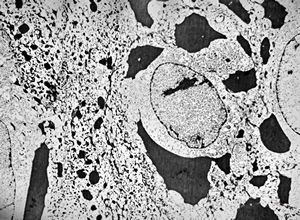

M, 60y. | otitis externa … microbes (fungi?) on the epidermal surface